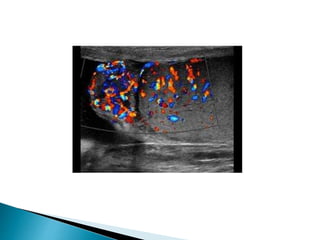

 On ultrasound varicoceles are seen as a

echo-free serpiginous structures measuring

more than 2 mm maximum diameter .

 Visible flow may he seen within larger

varicoceles.

 Their prominence is increased in the

upright position and with the Valsalva

manoeuvre.